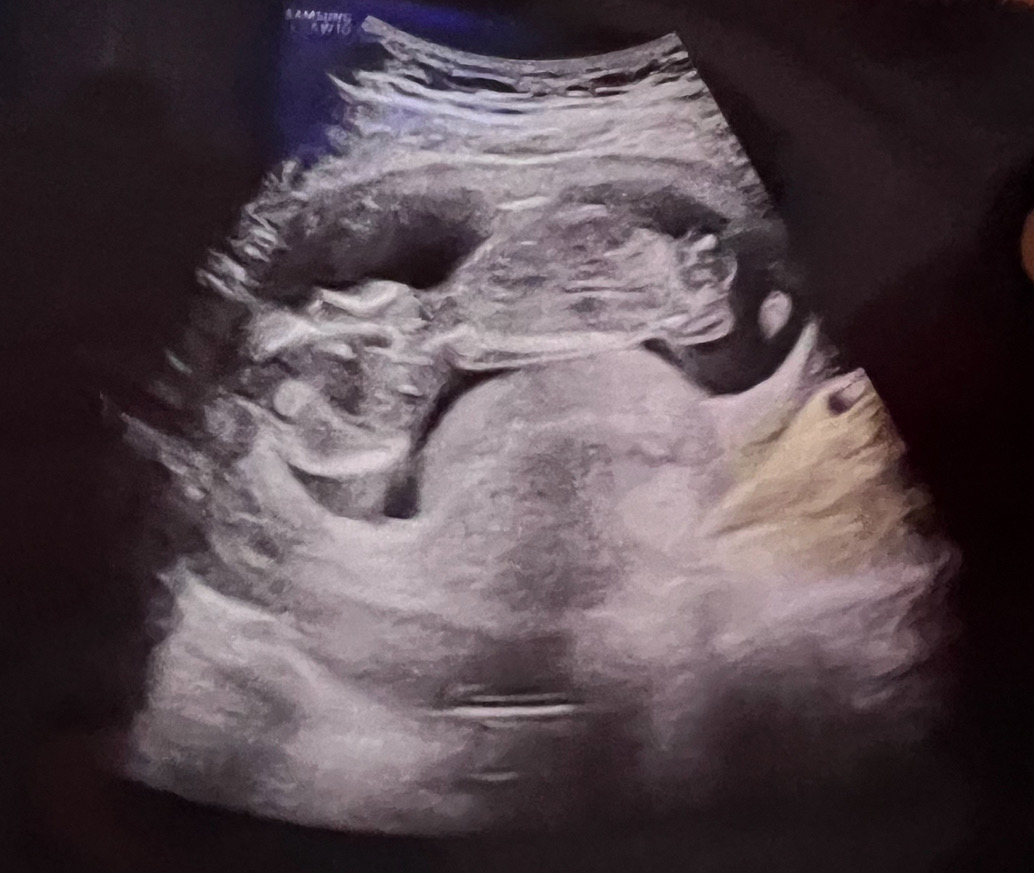

14주 초음파 봐주세용😀

혹시 초음파 어때보이시나요? 오늘 초음파 보고왔는데 병원에서는 별말없으셨는데 집에와서 보니 아기집 아랫쪽이 볼록하게 올라왔는데 왜 그런걸까요 ?ㅠㅠ 아기가 불편하지는 않을지 걱정되네요 첫임신이라 모르는게 많아요 ㅠㅠ

저두 어느 각도에서보면 안보이는데 어느각도에서 보면 저래서 궁금햇는데 의사쌤이 태반이라고 하시더라구용

저렇게 경추베개? 벤 초음파 사진들 그래도 꽤본거가타요! 넘 걱정마세요~